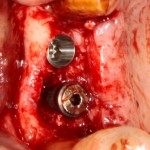

Другой вариант. Имплантируем, но существующего объема костной ткани недостаточно для получения адекватного эстетического и функционального результата:

Поэтому мы используем мембрану Geistlich BioGide и всё ту же аутокостную стружку:

Вот чем мне нравится мембрана BioGide — так это своими свойствами. Предсказуема до мелочей.

Во влажном состоянии она эластична и податлива, поэтому нет необходимости использовать пины или винты:

ну и, швы: